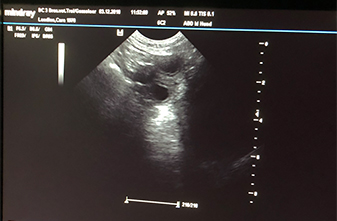

Heute war also der Tag der Tage. Der Tag an dem man Gewissheit bekommt, ob die Hündin aufgenommen hat oder nicht.

Auch wenn Caras Verhalten zu 100% für eine Trächtigkeit spricht, so wollten wir es gerne

von unserer Tierärztin Heike Trei absegnen lassen. :-)

Beim Ultraschall wurden auf Anhieb einige Fruchtanlagen gesichtet. Die genaue Anzahl wollte ich aber nicht wissen.... ein bisschen Spannung soll uns und den Welpeninteressenten schon noch in den kommenden Wochen erhalten bleiben. ;-) |

Wir freuen uns einfach riesig darüber, dass bald wieder kleine F-Racker den Bagalutenhof besetzen werden.

Bis dato werden wir Cara weiterhin fit halten und auf unser Essen aufpassen. :-)